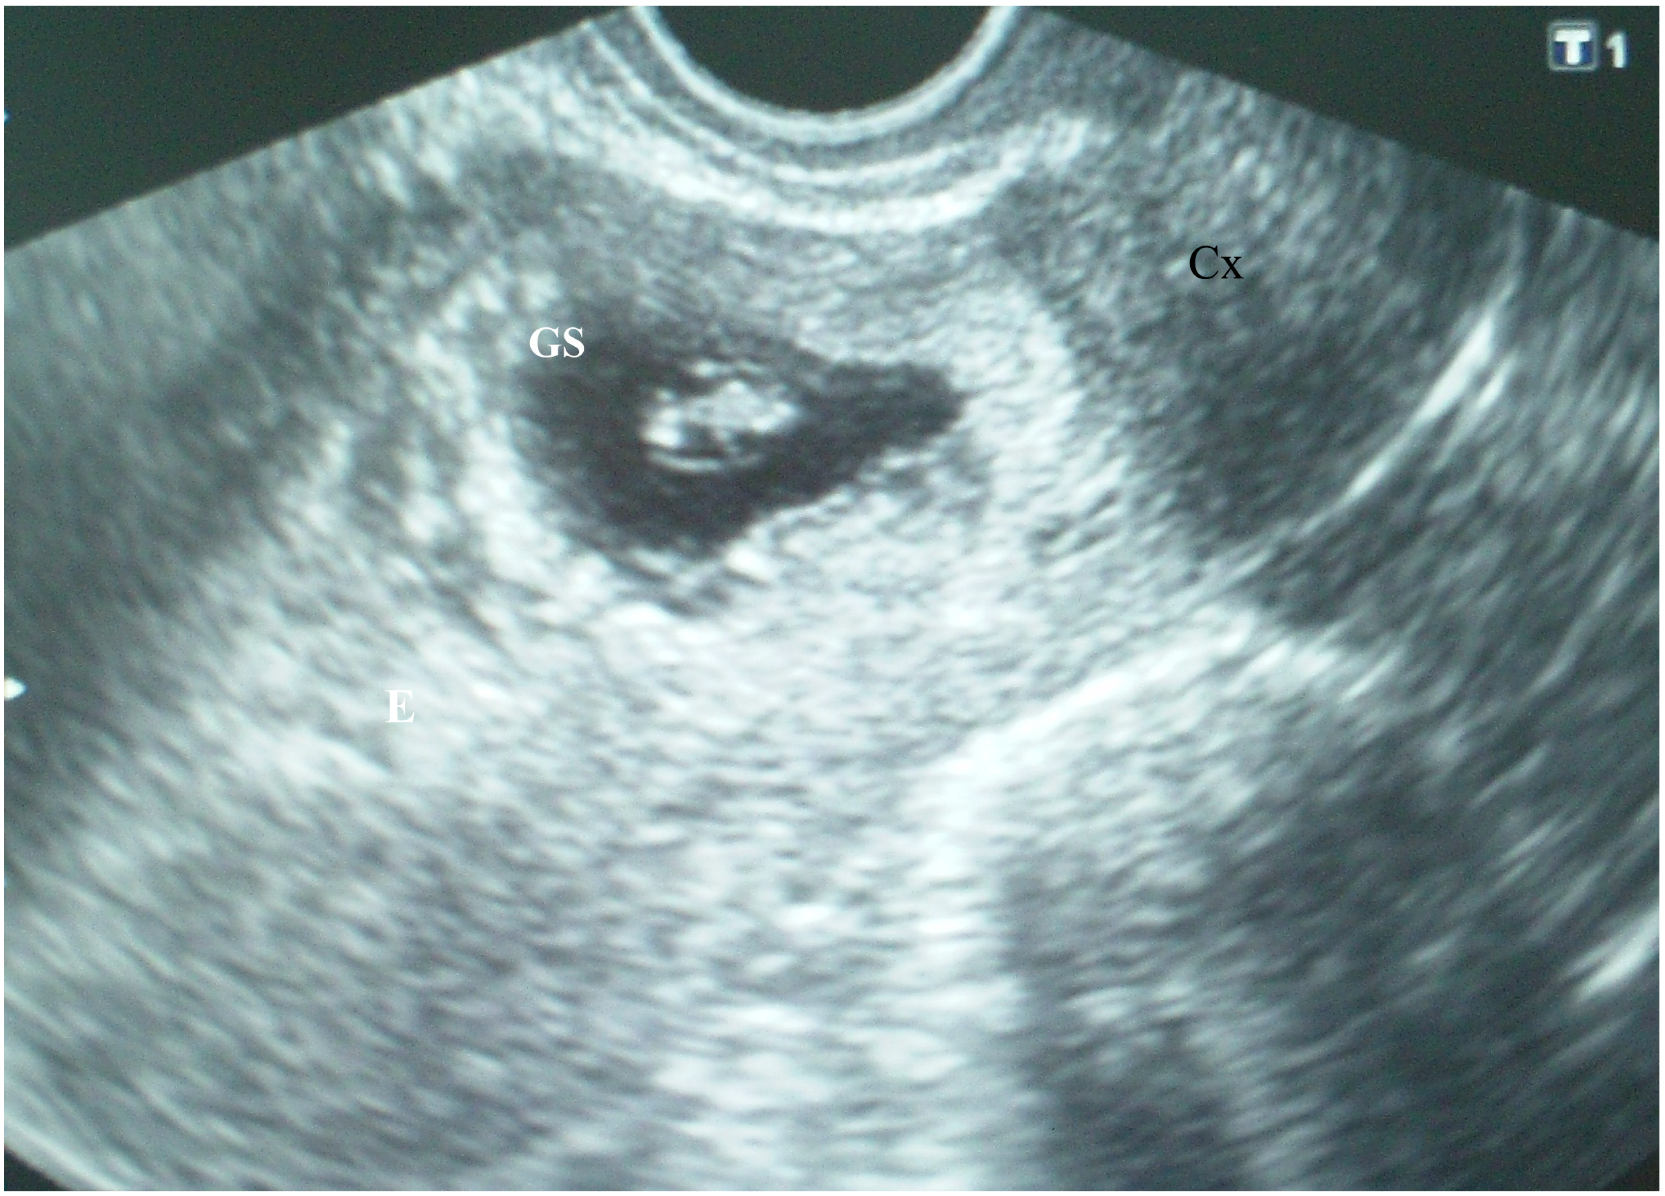

On admission, the patient was hemodynamically stable. An examination of her cardiac and respiratory systems was unremarkable. Her abdomen was soft without tenderness. A speculum examination indicated the presence of a single cervix with brown-colored discharge from the external os and no other pathological findings. Bimanual pelvic examination revealed an enlarged soft uterus corresponding to the sixth gestational week; the patient’s cervix was closed with no pathological adnexal findings. Transvaginal ultrasound examination (TVUS) [Toshiba Nemio XG, 6 MHz] showed an empty uterine cavity with a 9 mm endometrial strip and a triangular gestational sac (10 mm in diameter) located within the isthmic part of the anterior uterine wall that filled the niche of the scar, with a yolk sac inside (Figure 1). Both ovaries appeared sonographically normal, with a corpus luteum on the left ovary. There was no intraperitoneal fluid in the pouch of Douglas. A color Doppler ultrasound image of the cesarean scar gestational sac showed peripheral hypervascularity.

Figure 1.

Transvaginal ultrasound examination of a cesarean scar pregnancy (CSP) at the sixth postmenstrual week showing an empty uterine cavity with a 9 mm endometrial strip (E) and a triangular gestational sac (10 mm in diameter) located within the isthmic part of the anterior uterine wall filling the niche of the scar, with a yolk sac inside covered with a thin myometrial layer 2 mm in diameter (arrow); the cervical channel (Cx) is empty; according to the presence of cross over sign (COS), this gestational sac could be identified as COS-1; according to the implantation of the gestation sac it is implanted in the niche of the scar (ultrasound sign reported by Kaelin Agten et al.); according to the position of the center of the gestational sac it could be classified as implantation bellow the uterine midline (classification proposed by Timor-Tritsch et al.) (explanation in Discussion).

Another ultrasound grading system for cesarean scar pregnancy has been recently developed based on the location of the gestational sac and the amount of myometrium remaining [15]. Grade I CSP is defined as the gestational sac penetrating less than half of the myometrium, whereas grade II CSP is defined as penetration greater than a half the myometrium. In grade III CSP gestational sac develops outside the myometrium. In grade IV CSP, the pregnancy is difficult to identify; the gestational sac is highly vascular. According to the first ultrasound examination (Figure 1), the CSP of our patient could be classified as grade II.